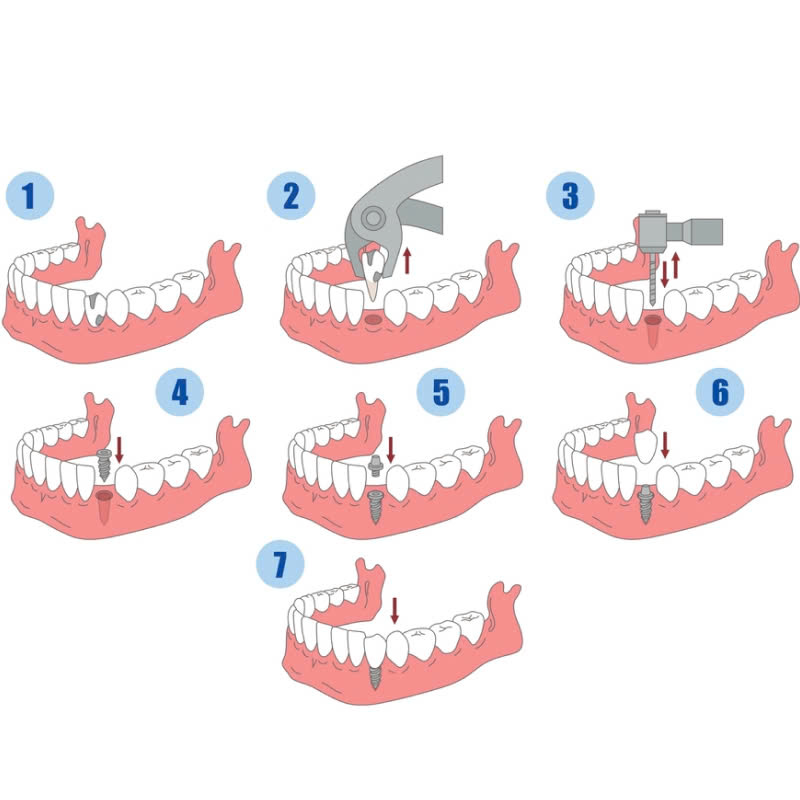

Quy trình trồng răng implant gồm các bước chính sau:

- Bước 1: Khám và tư vấn

Bác sĩ sẽ thăm khám, xác định tình trạng răng miệng, đánh giá sức khỏe tổng quát của khách hàng và tư vấn phương pháp điều trị phù hợp.

- Bước 2: Lấy dấu răng

Bác sĩ sẽ lấy dấu răng để tạo hình mão răng sứ phù hợp với răng thật.

- Bước 3: Cấy ghép trụ implant

Bác sĩ sẽ tiến hành cấy ghép trụ implant vào xương hàm, sau đó khâu vết thương.

- Bước 4: Thời gian liền xương

Trồng răng implant cần thời gian để tích hợp vào xương hàm, khoảng 3-6 tháng.

- Bước 5: Lắp mão răng sứ

Sau khi trụ implant liền xương, bác sĩ sẽ tiến hành lắp mão răng sứ lên trụ implant.